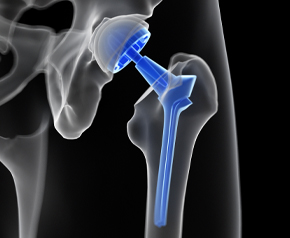

대퇴골두무혈성괴사

대퇴골두의 혈액순환 장애로 뼈 조직이 괴사되고 괴사된 뼈에 압력이 지속적으로 가해져 괴사부 위가 골절되면서 통증이 나타나는 질환입니다.

고관절을 인공관절로 교체

고관절 인공관절수술

수술적 치료

괴사가 많이 진행된 경우 손상된 관절을 인공관절로 대체하여 통증을 없애고 일상생활을 가능하게 합니다.